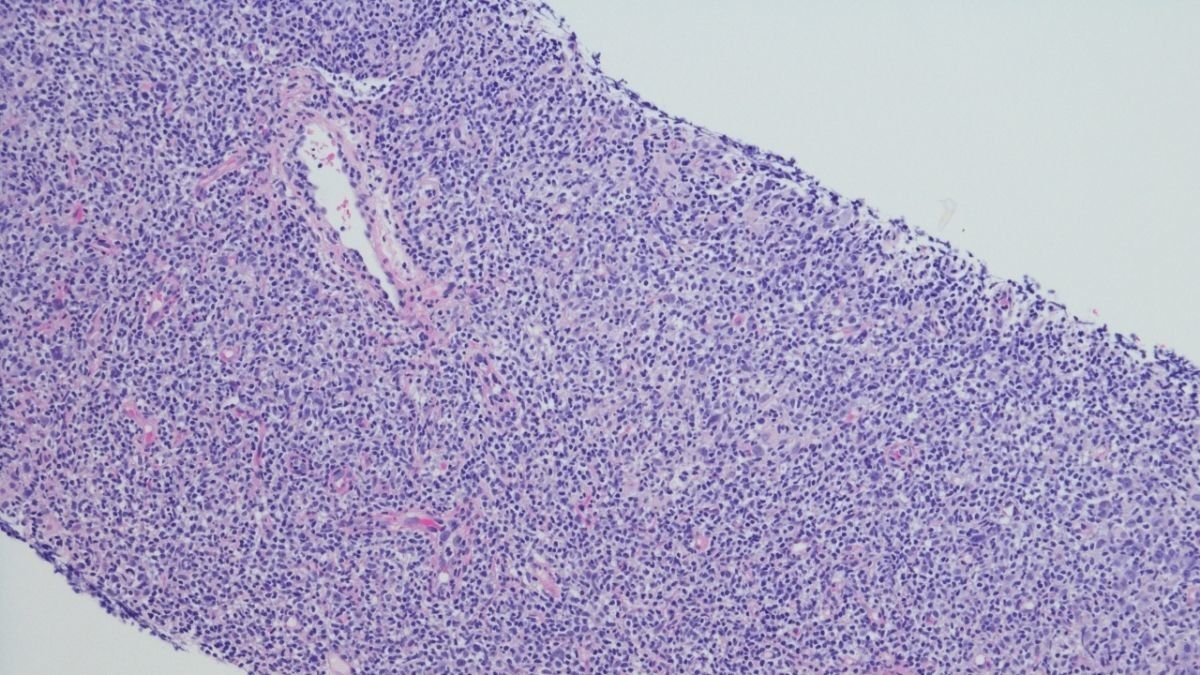

Berdasarkan Lymphoma Research Foundation, DLBCL merupakan jenis kanker non-Hodgkin atau kanker yang yang berkembang di sistem limfatik.

Umumnya, pertumbuhan kanker DLBCL berawal di limfosit B (salah satu jenis sel darah putih) yang bertugas memproduksi antibodi di kelenjar getah bening.

:format(webp)/article/OtOKdmXoq9taxxsOcKhII/original/089199800_1631169548-Kanker-DLBCL.jpg?w=256&q=100)